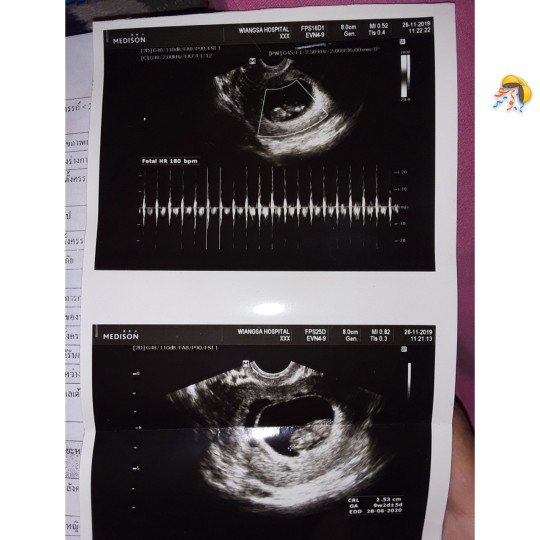

บ้านนี้ 8week ตัวเล็กไปมั้ยค่ะ☺️

ทีมสิงหาเหมือนกันค่ะ 8w 4d ค่ะ🥰